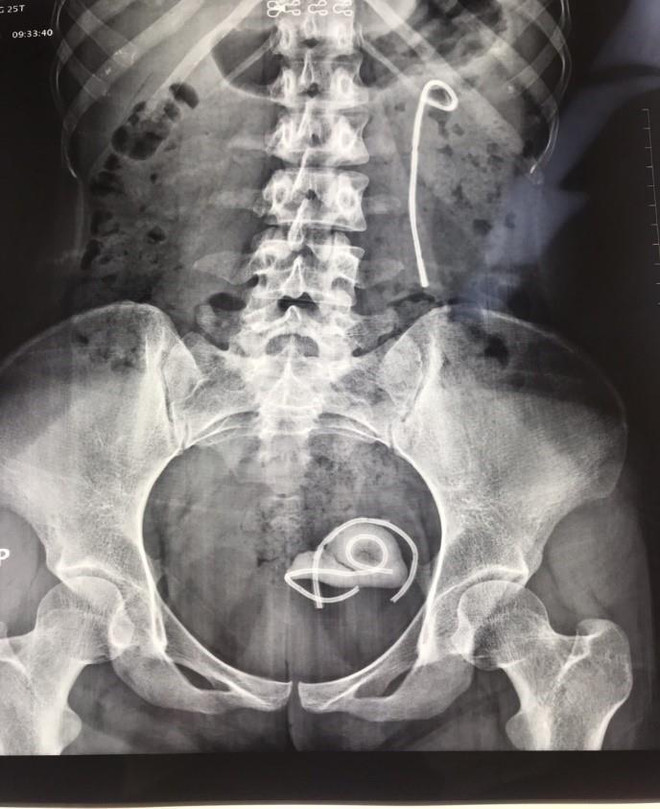

Bệnh nhân bị bỏ quên ống thông niệu quản suốt 5 năm ảnh 2Hình ảnh chụp X-quang của bệnh nhân. (Ảnh: PV/Vetnam+)

Stent bị bỏ quên trong cơ thể của nữ bệnh nhân trên đã bị gãy làm 3 đoạn: 1 đoạn trên thận, 2 đoạn trong bàng quang. Xung quanh stent jj có rất nhiều sỏi bám làm bệnh nhân đau buốt và mất máu, đặc biệt sỏi bàng quang với kích thước lớn hơn 3 cm.

Bệnh nhân bị bỏ quên ống thông niệu quản suốt 5 năm ảnh 1Rất nhiều viên sỏi và stent bị gãy làm ba đoạn. (Ảnh: PV/Vietnam+)